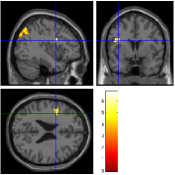

Once the reduced FOV images are available, the proposed pMRI 4D-UWR-SENSE algorithm and its early UWR-SENSE version have been utilized in a final step to reconstruct the full FOV EPI images and compared to the mSENSE Siemens solution. For the wavelet-based regularization, dyadic Symmlet orthonormal wavelet bases [48] associated with filters of length 8 have been used over resolution levels. The reconstructed EPI images then enter in our fMRI study in order to measure the impact of the reconstruction method choice on brain activity detection. Note also that the proposed reconstruction algorithm requires the estimation of the coil sensitivity maps (matrix in Eq. (2)). As proposed in [4], the latter were estimated by dividing the coil-specific images by the module of the Sum Of Squares (SOS) images, which are computed from the specific acquisition of the -space centre (24 lines) before the scans. The same sensitivity map estimation is then used for all the compared methods. Fig. 5 compares the two pMRI reconstruction algorithms to illustrate on axial, coronal and sagittal EPI slices how the mSENSE reconstruction artifacts have been removed using the 4D-UWR-SENSE approach. Reconstructed mSENSE images actually present large artifacts located both at the centre and boundaries of the brain in sensory and cognitive regions (temporal lobes, frontal and motor cortices, …). This results in SNR loss and thus may have a dramatic impact for activation detection in these brain regions. Note that these conclusions are reproducible across subjects although the artifacts may appear on different slices (see red circles in Fig. 5). One can also notice that some residual artifacts still exist in the reconstructed images with our pipeline especially for . Such strong artifacts are only attenuated and not fully removed because of the high level of information loss at .

| mSENSE | 4D-UWR-SENSE | ||

| Axial |  |

|

|

| Coronal | |||

| Sagittal | |||

| Axial |  |

|

|

| Coronal | |||

| Sagittal |